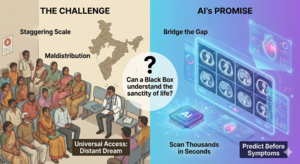

Beyond the Black Box

Beyond the Black Box:

Beyond the Black Box

Beyond the Black Box: